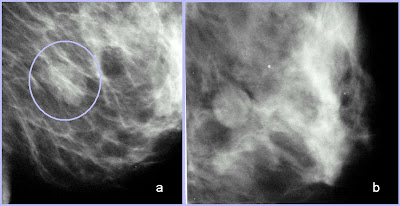

- Distorção focal de arquitetura: espiculações em uma região da mama ou uma retração focal do contorno parenquimatoso denso.

- Distorção focal da arquitetura, comprovadamente não associada à cirurgia prévia.

Recomendações: biópsia percutânea e correlação anátomo-patológica.